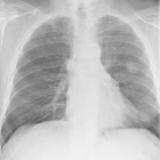

Case 9 Thymoma PA

Date: 04/04/2010

Views: 3169

Case 9 Thymoma Lat

Views: 3173